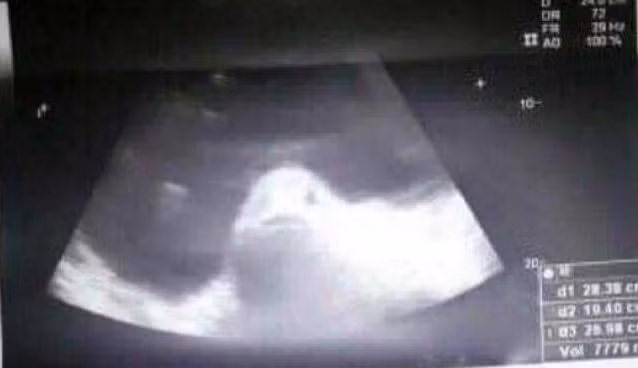

| Hình ảnh siêu âm khiến dân làng càng tin rằng Kimberly đang mang thai với cá. Ảnh: GMA News |